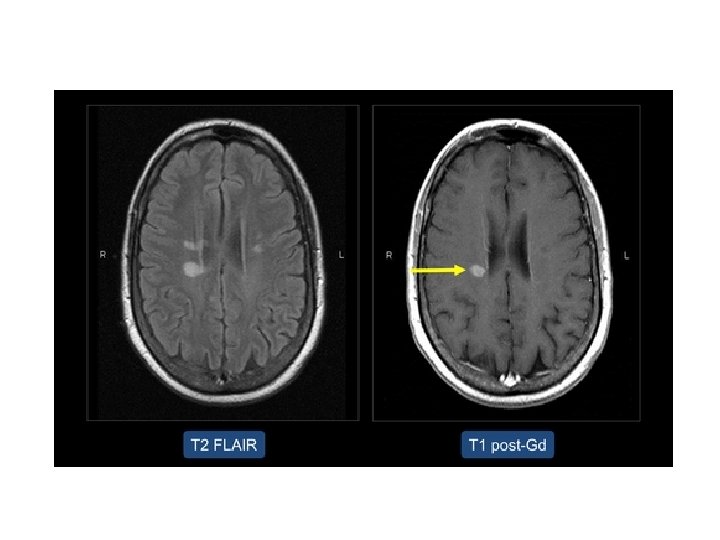

MRI • Klinik bulgular olmaksızın anormal MRI MS tanısını konfirme etmez • Klinik olarak kesin MS olan hastada anormal MRI olmaması tanıyı dışlamaz

MRI BULGULARI • Periventriküler ak maddede plaklar • Serebellum / beyinsapı / servikal ve torakal spinal kord • Kontrast madde (Gadolinium) tutulumu aktif lezyon varlığını gösterir – Her zaman hastalık aktivitesinde artış ile korelasyon göstermez

MRI • MRI anormalliği: – Kesin MS’de %90 – Olası MS’de % 70